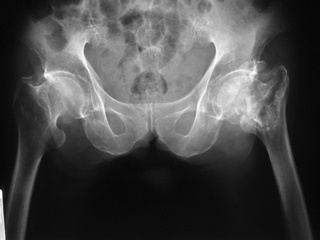

ภาพรังสีแสดงการยุบของกระดูกสันหลังหลายระดับ วิธีการดู คือ จะสังเกตจากความสูงของกระดูกสันหลังเทียบกันในแต่ละระดับ จะพบว่าส่วนของกระดูกสันหลังที่ยุบลงนั้นจะมีความสูง

ของกระดูกสันหลังลดลงเมื่อเทียบกับกระดูกสันหลังที่อยู่ติดกัน